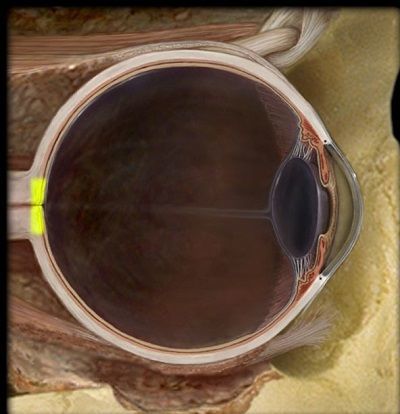

Question 3

Question

¿Qué estructura esta señalada?

Image:

d6e887c8-6c5e-4242-a367-7ba3c83cc636 (image/jpeg)

Answer

Cristalino

Retina

N. Optico

Pulia

Córnea